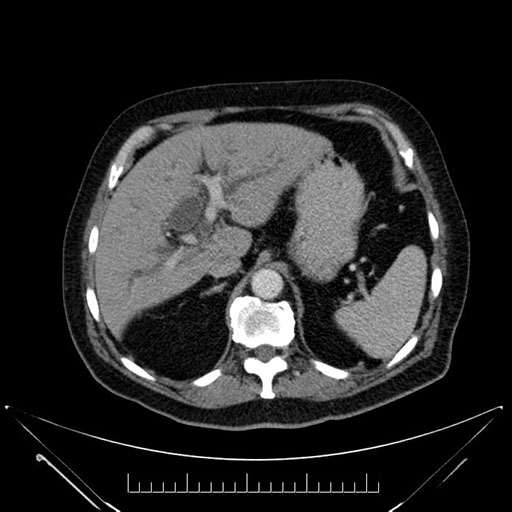

Imaging Analysis

Look through the patient's CT scan to identify any areas of concern for the necessary procedure.

Based on your CT findings, which issue(s) would give reason for "planned slowing down moment(s)" in this case?